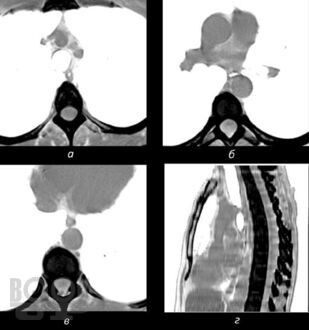

В книге изложены основные сведения по анатомии и патофизиологии пищевода и кардии, освещены вопросы клиники, диагностики, консервативного и оперативного лечения их хирургических заболеваний. С учетом последних достижений медицинской науки и практики описаны нервно-мышечные заболевания пищевода, гастроэзофагеальная рефлюксная болезнь, злокачественные новообразования, травмы, ожоги, болезни оперированного пищевода. Особое внимание уделено хирургической тактике и технике оперативных  вмешательств.